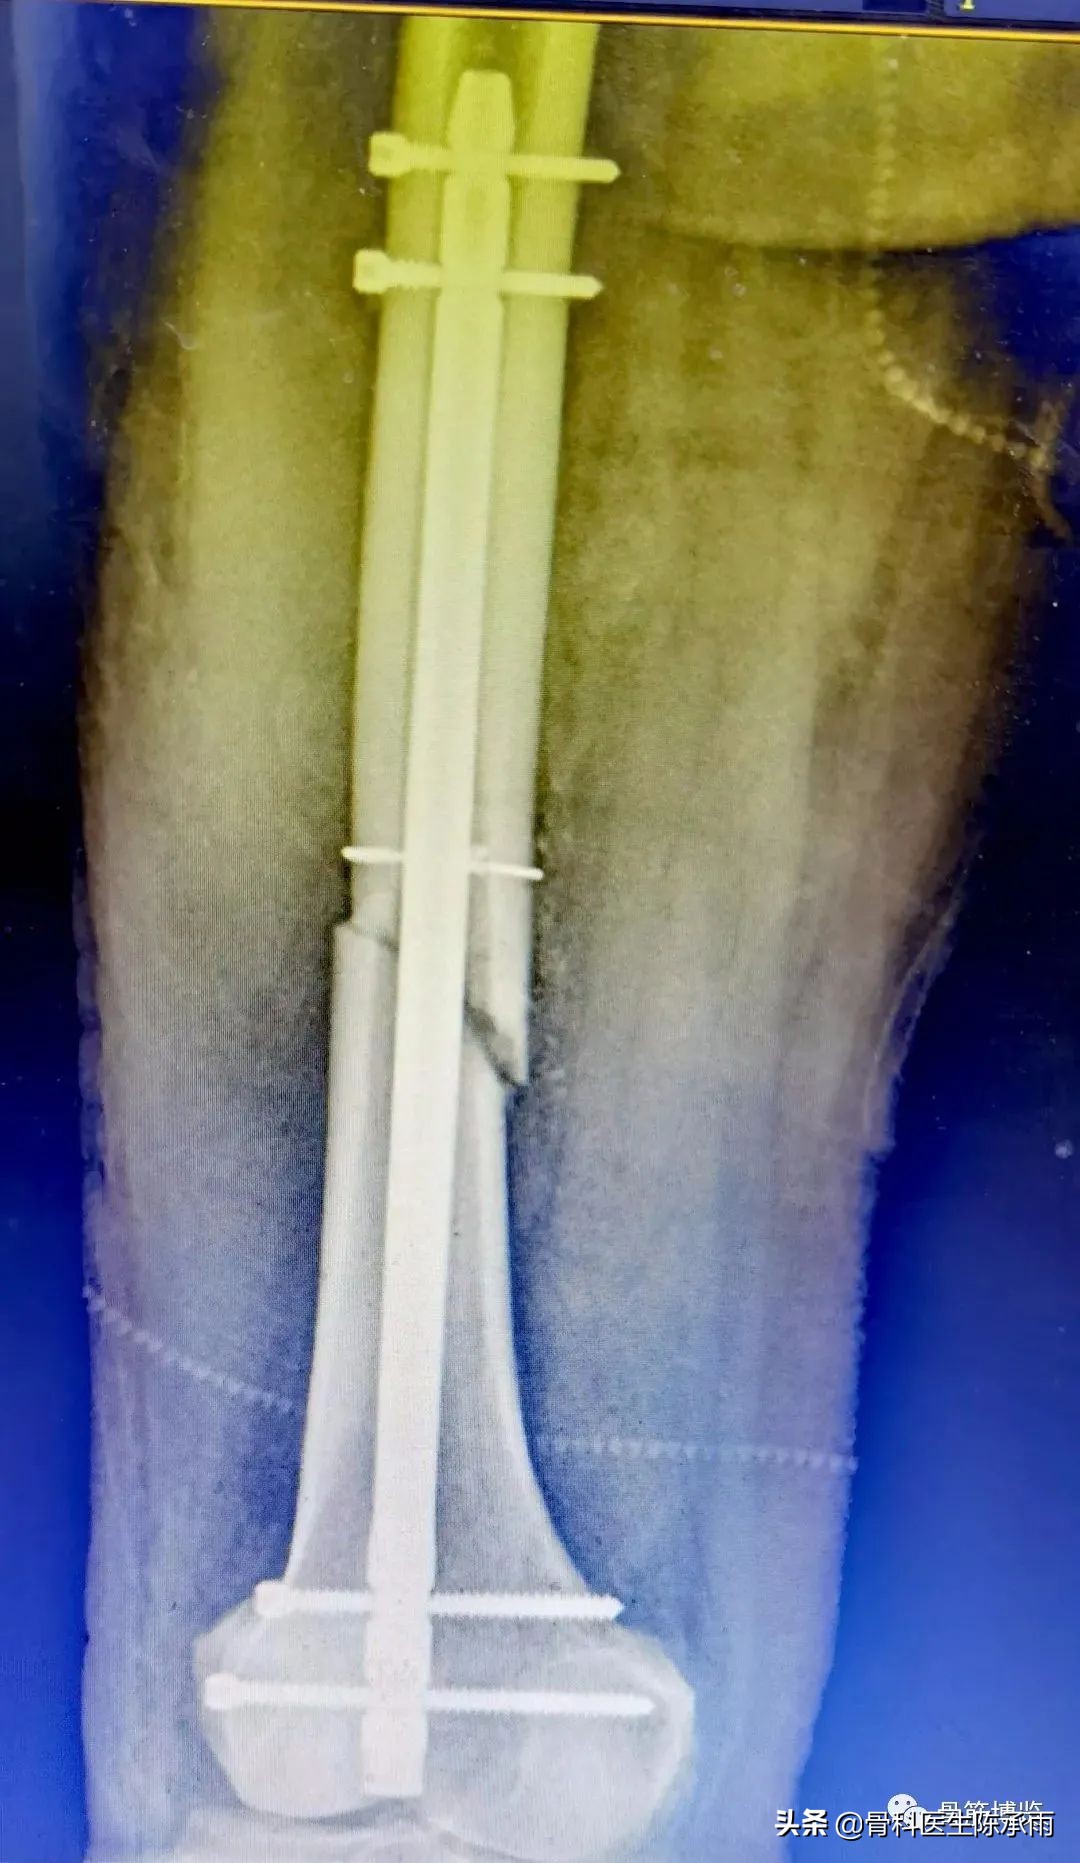

这2例患者皮肤条件差,全身多发骨折,小腿皮肤条件差,1例筋膜高压切开,1例整个小腿布满张力性水泡,胫骨骨折都在伤后30天才能手术。